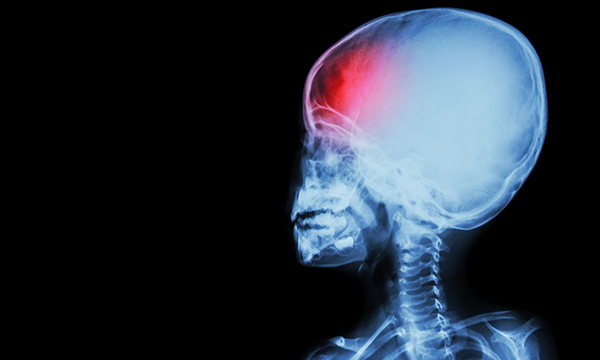

Trialled use of steroids to prevent childhood stroke is justified, concludes an extensive review of recent reports.